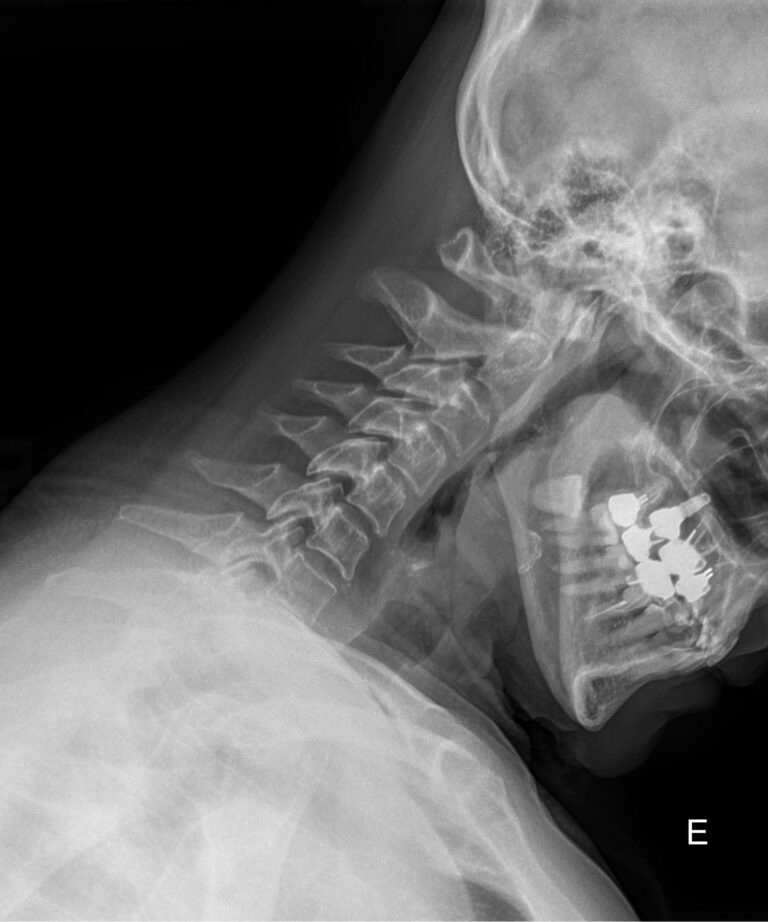

Процедура не требует специфической подготовки. Однако необходимо снять с шеи и головы все металлические предметы: украшения, съемные медицинские гаджеты и предупредить о несъемных. Затем надеть защитный фартук. Далее надо сесть или встать возле пластины детектора и прижать к ней голову, как покажет рентгенолаборант: носом и лбом, носом и подбородком или только подбородком, это зависит от того, какие пазухи подлежат съемке. Так как пазухи парные, то есть расположены симметрично, голову нужно держать ровно, не поворачивая и не отклоняя вправо или влево. Если будет указано в направлении, выполняется несколько снимков в разных проекциях, чтобы были видны разные пазухи.